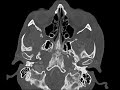

Mandibular Condyle Osteochondroma

These images demonstrate a small non-articulating exostosis emanating from the anteromedial aspect of the right mandibular condyle. The cortex and medullary bone is contiguous with that of the mandibular condyle. Findings are most compatible with a small osteochondroma. The coronoid process and condyle are the most common sites for lesions affecting the jaw. The differential would include osteophyte in degenerative joint disease, condylar hyperplasia, and osteoma. Larger lesions may result in facial asymmetry and abnormal bite.